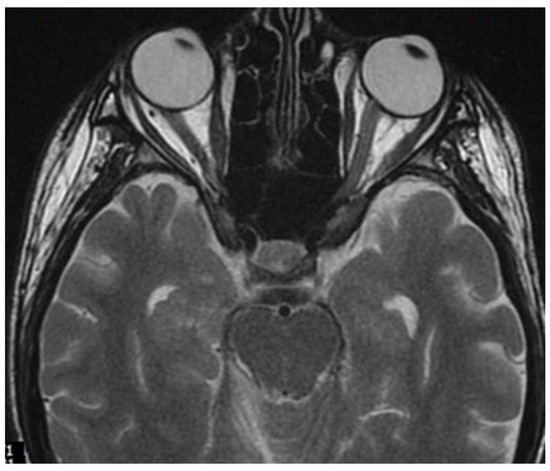

During hospitalization in the neurology ward, Holter EEG was performed in which seizure episodes corresponded to changes in the recording. Interictal EEG showed rapid activity followed by slow theta waves and several sharp and slow wave complexes (Figure 1 and Figure 2). Topiramate was added to valproic acid at a target dose of 2 mg/kg of body weight. Gradual seizure relief was observed in the following weeks, and there were no other neurological manifestations for another nine months. After that time, in December 2021, the patient was admitted to the pediatric ward due to impaired consciousness and persistent vomiting, followed by paresis of the lower limbs. A brain MRI was performed, which showed “T2/FLAIR images reveal poorly defined areas of increased signal in the brain’s white matter, both above and below the tentorium, as well as in the periventricular and subcortical regions. These areas correspond to low signal regions in T1 images. The largest change area measures 19 × 14 mm and is located in the right middle cerebellar peduncle, which merges with changes observed in the pons. Additionally, there is a lesion in the right thalamus, measuring 10 × 24 mm, along with numerous scattered foci in the corona radiata and between the basal nuclei. Overall, the imaging findings primarily suggest acute disseminated encephalomyelitis (ADEM)” (Figure 3 and Figure 4). Cerebrospinal fluid examination revealed oligoclonal bands and an elevated protein level of 118.5 mg/dL (reference range: 15.0–45.0 mg/dL) and a slightly elevated leukocyte level of 29/mm3 (lymphocytes 72.4%, neutrophils 27.6%).

Figure 4.

Transverse FLAIR brain magnetic resonance image showing area of increased signal in the right middle cerebellar peduncle (December 2021).